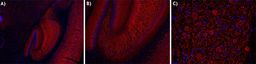

Alexa Fluor® 594 anti-MAP2; Clone: SMI 52; Reactivity: Mouse, Rat; Apps: IHC-P; Size: 100 μg